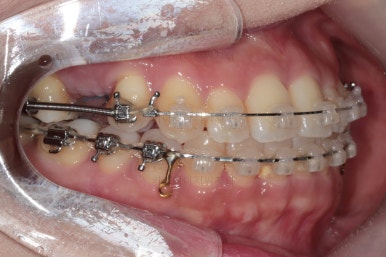

장치를 부착한 모습 참고해 주시고요.

아랫니는 중앙선을 맞추기 위해서 미니스크류를 이용해 한 쪽으로 당기는 중이고요.

이 과정에서 아랫니들이 약간은 뒤로 들어가져서 아랫입술 부위의 돌출감을 아주 약간은 줄일 수 있습니다.

윗니 임플란트 할 자리는 적절히 계속 맞춰줍니다.

중앙선도 점점 맞아지고 있어요.

임플란트 할 공간도 여유롭게 마련이 되었네요.

임플란트는 뿌리 부분 식립 -> 3~6개월 기다림(뼈와 임플란트가 단단히 붙을 시간이 필요) -> 머리 부분을 완성하고 마무리

따라서 교정치료가 100% 끝나기 전에, 임플란트 공간만 마련되면 바로 식립을 하게 됩니다.

임플란트 뿌리 부분이 먼저 식립되었고요.